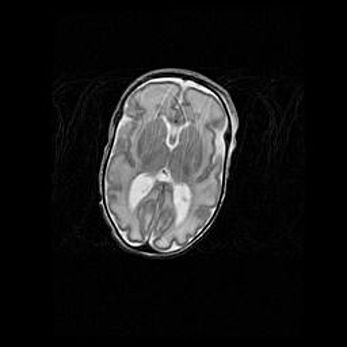

Подострая гематома правой гемисферы мозжечка.

Наружная гидроцефалия.

Возраст: 15 дней

Вес: 3100 г

Пол: женский

Окружность головы: 37 см

Срок гестации: 35-36 недель

При открытой наружной форме гидроцефалии у новорожденных расширяются и переполняются субарахноидные пространства.

Кровоизлияния в мозжечок имеют две клинико-анатомические формы: полушарные гематомы и кровоизлияния в червь.

К появлению этой патологии может привести: повреждения головного мозга, возникающие в результате асфиксии и гипоксии плода при беременности, или травмы во время родов. Редко гематома мозжечка может быть результатом первичной коагулопатии и сосудистой мальформации, диссеминированном внутрисосудистом свертывании, изоиммунной тромбоцитопении.